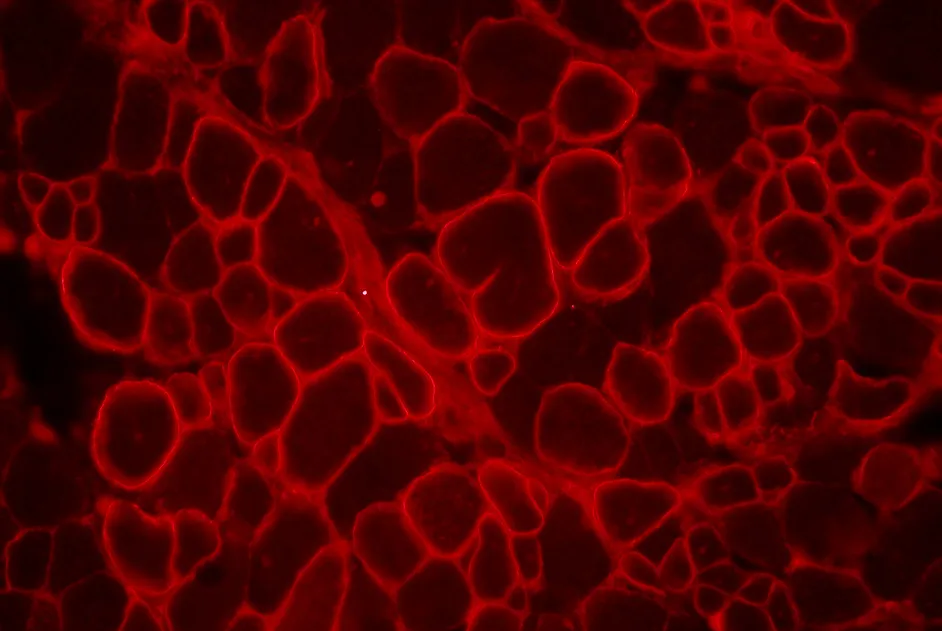

Une étude menée chez des adultes atteints d’amyotrophie spinale proximale liée à SMN1 retrouve une atteinte du cervelet à l’imagerie, sans aucun symptôme.